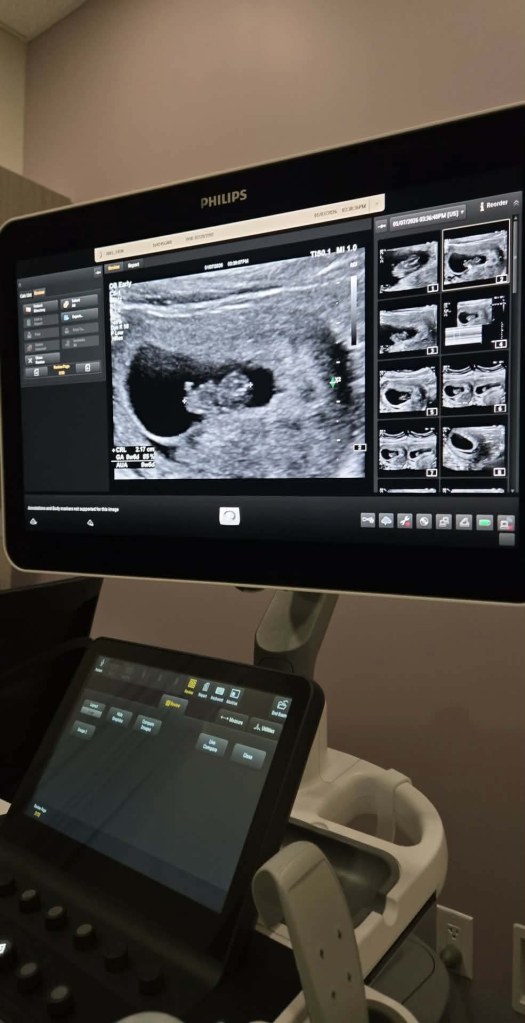

We’ve been quietly going through the process again since mid-last year, keeping our hopes high, but still appreciating that nothing about these bumpy roads is ever guaranteed.

Remarkably, Erin has birthed another surro baby since having Ernie, so we waited patiently until she and her body were ready to do this once again. Knowing that Erin is carrying for us again has made this journey feel safe, predictable and all the more exciting given when we see Erin next, not only will that mean our new arrival is imminent, but Ernie will be reunited with her nearly four years since he entered the world himself. We’ve said it before, and we’ll say it again, but there are no adequate words to express our gratitude for the extent to which Erin has changed our lives. She knows how we feel; we’re in awe of what she’s doing.